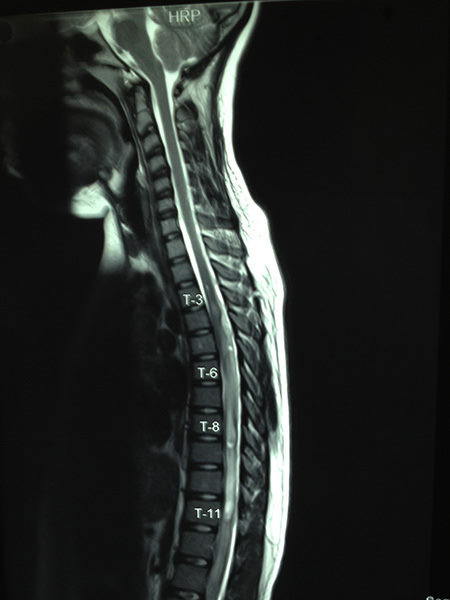

.

Casos Neuroloquirúrgicos

Envíado por Dr. Ruben Eduardo Amaya Contreras